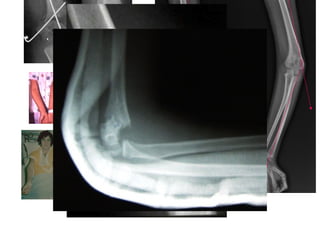

ELBOW DISORDERS

Anatomy Elbow

Humerus:

Trochlea

Capitulum

Coronoid Fossa

Medial & Lateral Epicondyle

Radius:

Radial head

Radial neck

Radial tuberosity

Radial Fossa

Ulna:

Coronoid Process

Olecranon Process

Ulna Tuberosity